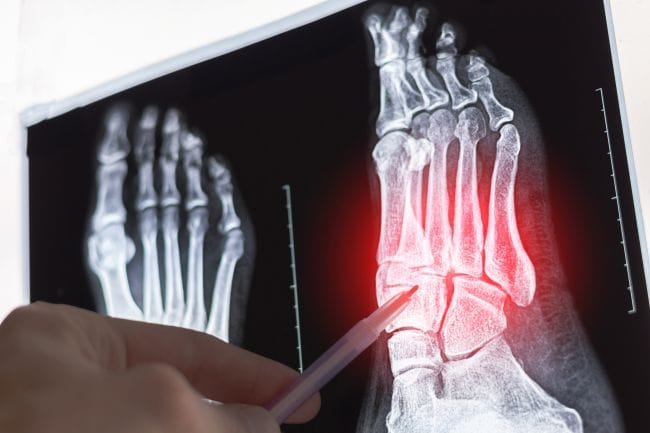

Cedera yang Sering Terjadi pada Tulang Metatarsal

Cedera tulang metatarsal cukup umum, terutama pada orang yang aktif. Berikut beberapa jenis cedera yang perlu diwaspadai:

1. Fraktur stres (retakan kecil)

Fraktur stres terjadi saat tulang metatarsal mengalami tekanan berulang secara terus-menerus, misalnya karena sering berlari jarak jauh, melompat, atau berdiri lama dalam aktivitas sehari-hari. Retakan kecil ini biasanya tidak langsung terlihat, tapi dapat menimbulkan rasa nyeri di bagian tengah kaki yang makin terasa saat digunakan untuk berjalan atau berlari.

Gejala lainnya meliputi pembengkakan, kadang-kadang kemerahan, dan rasa tidak nyaman saat menggunakan sepatu. Jika tidak ditangani dengan baik, fraktur stres bisa berkembang menjadi patah tulang.

2. Fraktur akibat benturan langsung

Cedera ini terjadi ketika kaki mendapat benturan keras, seperti tertimpa benda berat, terjatuh, atau terkena hantaman saat olahraga. Fraktur akibat benturan langsung biasanya menyebabkan nyeri hebat yang mendadak, bengkak yang cukup besar, dan kemungkinan muncul memar di area yang terkena.

Pada beberapa kasus, bentuk kaki bisa tampak berubah atau terdapat tonjolan yang tidak biasa. Cedera jenis ini membutuhkan pemeriksaan dokter secepatnya agar tulang bisa kembali pada posisinya dan sembuh dengan benar.